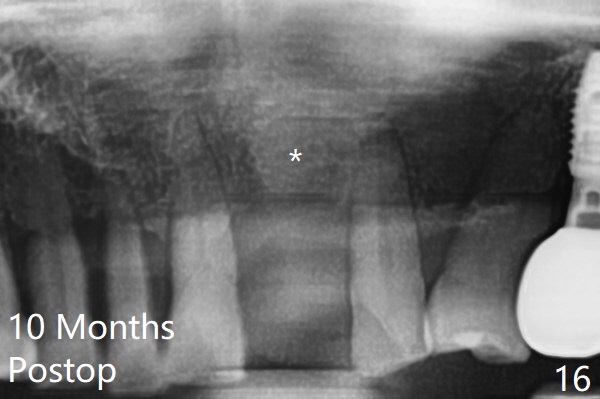

A 67-year-old man requests extraction of the loose tooth #9 (Fig.1). After extraction, the labial plate is found to be missing. With incision, allograft is kept in place with a 12x24 mm anterior narrow Cytoplast and 4-0 Chromic gut suture (Fig.2). Periodontal dressing dislodges in 2 days. The wound dehisces transversely 5 days postop (Fig.3 arrows), whereas the wound was open buccopalatal when the sutures were placed. Probably due to extensive dissection, the erythematous mucosa is large (Fig.4), although asymptomatic. When X-ray shows V-shaped bony defect (Fig.1 (PA), 5 (Pan), 6 (CT)), do not dissect the overlying thin buccal gingiva, which is most likely to dehisce. In fact immediate implant with guide appears to be more conservative, since there is no pressure against the buccal gingiva (Fig.7,8). To be more ideally, the implant could be placed more coronally, longer (13 mm instead of 11.5, Fig.9,10) and narrower (3.5 mm instead of 4.0 mm, Fig.11 (red circles: bone graft)).